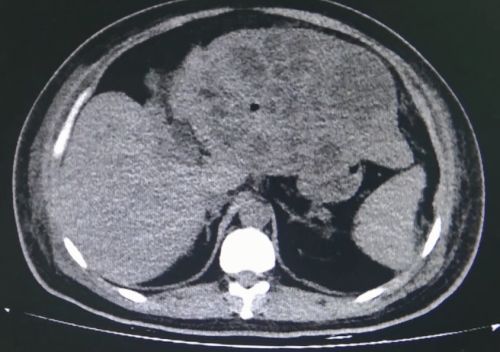

ct上可以看到左肝上布满脓肿。

在杨尽晖主任医师的安排下完善相关检查后,明确龙廷邦是由于肝内外胆管结石嵌顿造成胆管炎、胆总管梗阻、胆汁性肝硬化、脾脏肿大,严重的炎症导致脓毒血症、腹膜炎、肺部感染、胸腔积液、低蛋白血症、毛细血管渗漏综合征,左肝有数十个大小不一的脓肿,肝脏肿大至正常的六倍,心、肝、肺、凝血功能等全身多脏器功能不全,体重104公斤却重度贫血、营养不良,医生预言:“如果不手术活不过3天”。